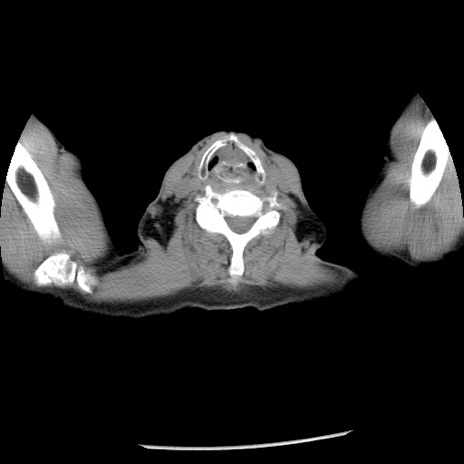

症例26(横断像)

【症例】80歳代男性

【主訴】嘔吐

【現病歴】昨晩2回嘔吐あり、今朝になっても嘔吐あり。来院。

【既往歴】胃潰瘍

【身体所見】意識清明、BT 37.6℃、BP 166/95mmHg、HR 100bpm、SpO2 97%、腹部:平坦・軟、腸蠕動音聴取良好、圧痛なし。

【データ】WBC 21900、CRP 1.46